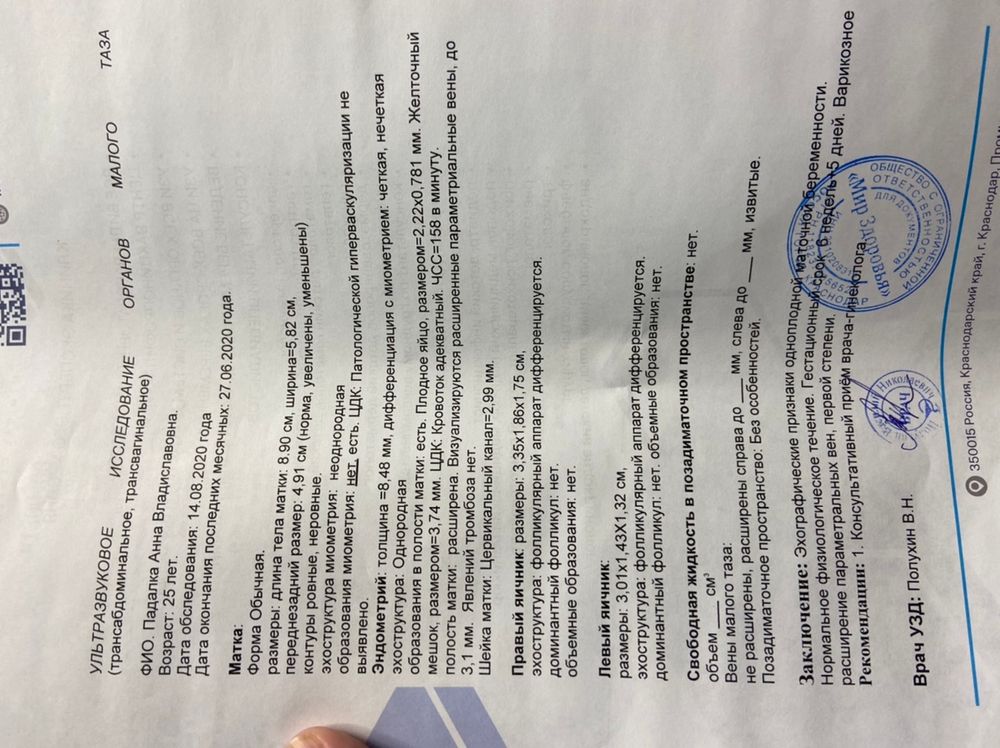

Была 8 дней назад на узи, ктр был 1,8. Сб ещё не было, но увидели пульсацию слегка. Сегодня сходила к другому специалисту, тк к той не было записи долго. Узист сказал все прекрасно, кроме расширения моих вен. Но когда я вышла из кабинета увидела что ни ктр, ни чсс не указано, вернулась, он сказал что чсс забыл дописать(дописал 158? Это норма? По таблицам много), а ктр на таком сроке не смотрят, смотрят кровоток и жм 🤷🏽♀️🤷🏽♀️🤷🏽♀️Но как тогда он ставил срок 6+3 без ктр, сказал программа выставила и это точный срок. узи за сегодня и фото за сегодня, так же и прошлое узи вставлю для ясности. Посмотрите пожалуйста, иначе я с ума сойду до скрининга 🤦🏽♀️🤦🏽♀️🤦🏽♀️ Вообще не планировала больше на узи до скрининга идти, но теперь ещё непонятнее чем было